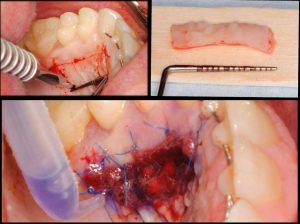

Objetivos periodontales: Mediante ingerto de tejido conectivo subepitelial de paladar con técnica de tunelización.

- Injerto de tejido conectivo libre desepitelizado de paladar + Tunelización

Fotografías del proceso: